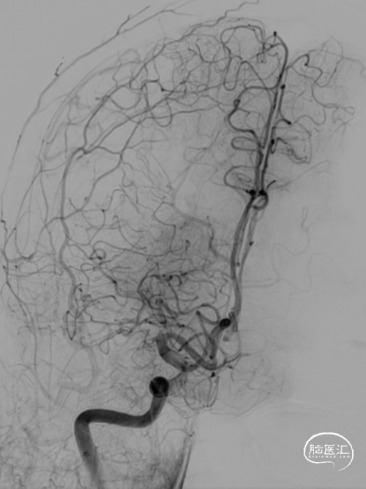

手术过程

路径困难是导致困难取栓的常见原因之一,既往因为普通导引导管较硬而无法通过迂曲血管到达目标血管,并增加手术时间。同时既往中间导管通过性能差而无法顺畅的实现高到位并进行抽吸,两者大大降低了取栓效率。普微森MidAccess™导引导管 088-90 cm具有8F普通导引导管直径,通过性能明显优于普通导引导管,特别是在该病例RCCA如此迂曲的情况下,仅在泥鳅导丝引导下就可以顺利通过Z字型迂曲到达C1段,为后续068中间导管提供了有力支撑并缩短的取栓距离。普微森MidAccess™导引导管 068-132 cm具有口径大、高到位、耐疲劳的特点,在微导管微导丝引导下3次顺利通过眼动脉段并送至RMCA起始段及M1中远端进行抽吸,不仅缩短了取栓时间,也避免了反复支架取栓对血管管壁的损伤。